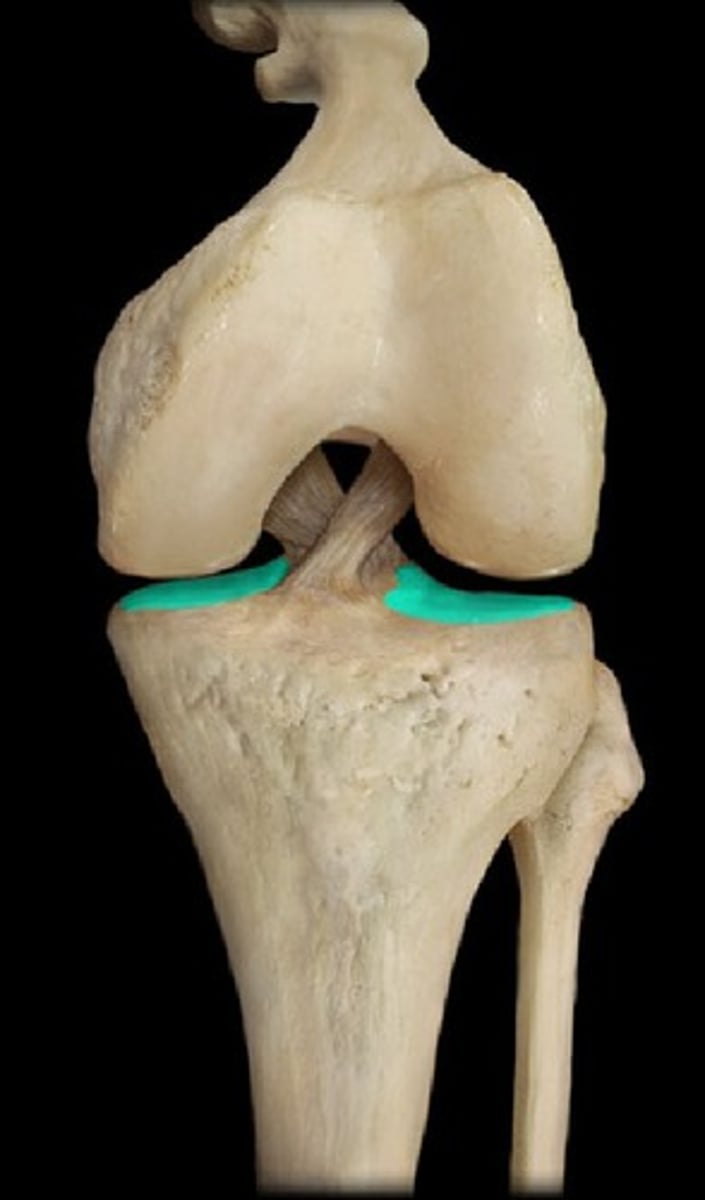

tibial plateau

medial condyle of tibia

lateral condyle of tibia

intercondylar eminence of tibia

superior fibular articular facet

(blank) major weight bearing of the leg

tibia

(blank) articulates proximally with femur, twice laterally with the fibula , and distally with talus

tibia